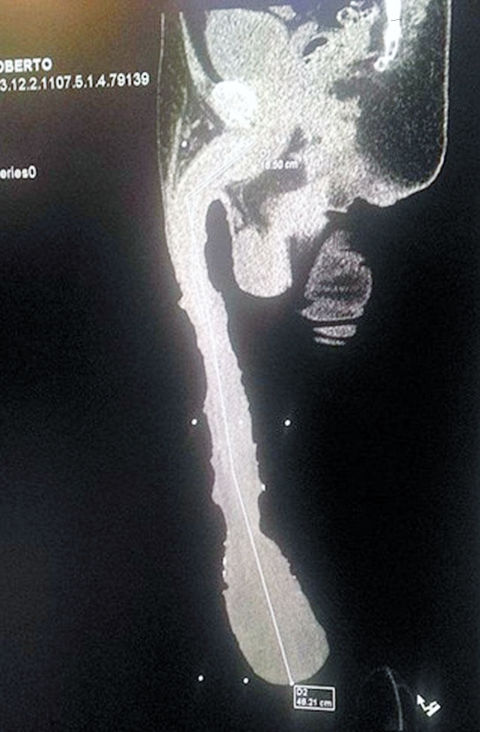

Who has the biggest penis in the world? Jonah Falcon or Roberto

Who has worlds biggest penis? Jonah Falcon or Roberto Esquivel Cabrera?